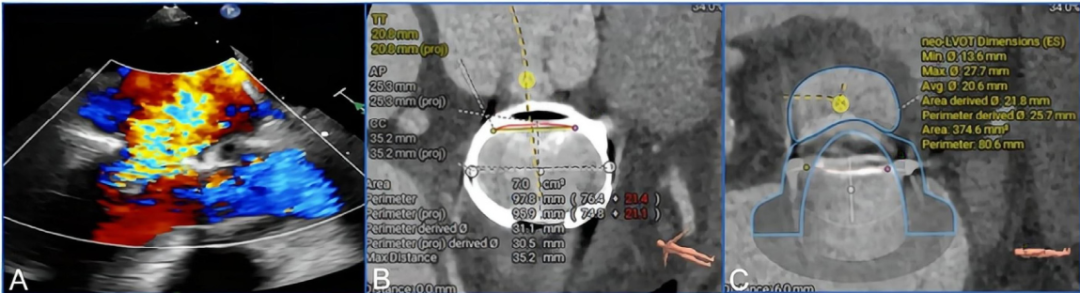

Professor Yang Jian’s team at Xijing Hospital conducted a detailed assessment of the patient’s transesophageal echocardiography (TEE) and CTA images, considering the patient’s significant symptoms and the extremely high risk of re-thoracotomy (STS score 11.192%; EuroSCORE II score 8.3%), ultimately deciding to perform TMViR (see Figure 1A–E).

Figure 1. (A-E) Preoperative imaging assessment.(A) Preoperative echocardiography indicated severe mitral regurgitation. (B–E) Preoperative CTA was used to assess the mitral valve annulus and left ventricular outflow tract structure. (B) The area of the mitral valve repair ring was 7.0 cm². (C, D) After simulating the implantation of the Mi-thos biological valve, the new left ventricular outflow tract area was 374.6 cm², with no obstruction observed. (E) The projection angle for valve implantation during surgery was RAO 46°, CAU 22°.

3. Based on the preoperative 3D printing model simulated assessment created from the patient’s individual CTA data (Figure A–C).

Figure A-C: Preoperative simulation using 3D printing (A) Adjusting the valve release position and its coaxial alignment with the annulus. (B, C) The biological valve fully deployed, observable from both left atrial and left ventricular perspectives.